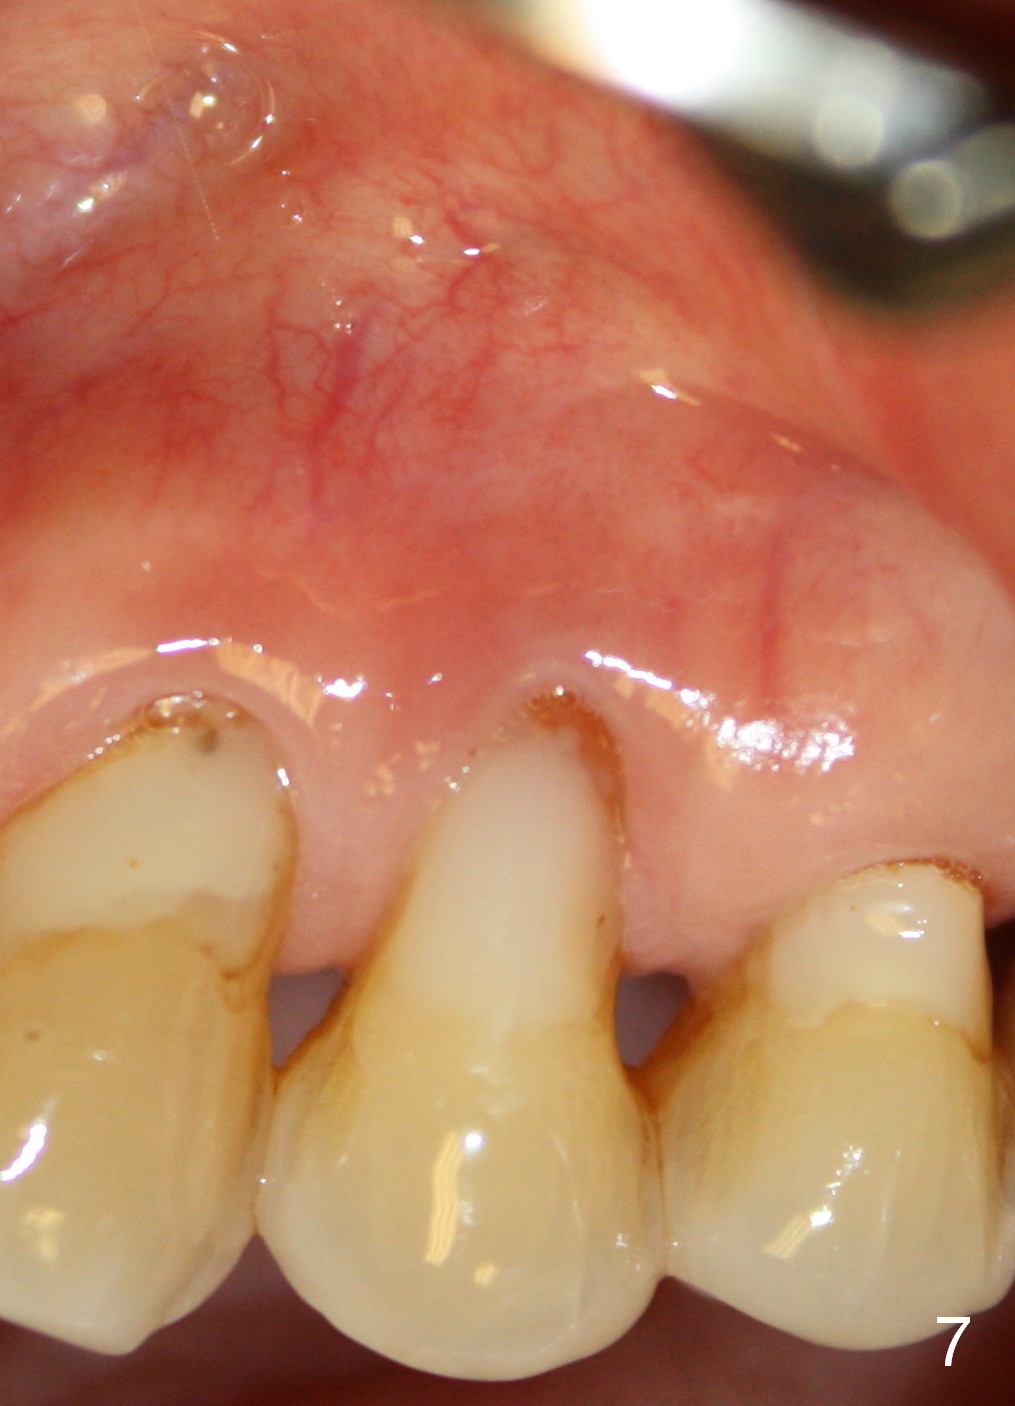

A 72-year-old lady has a deep cervical defect of the tooth #12 (Fig.1 ^) associated with buccal apical fistula (*) and periapical radiolucency (Fig.2 *). To prevent bleach leakage during root canal therapy (RCT), composite is used to repair the defect (Fig.3 (CT coronal section) C) prior to access. The buccal canal is not located probably due its own or iatrogenic (due to composite) obliteration. After thorough debridement of the lingual canal, Calcium Hydroxide paste is placed (*).